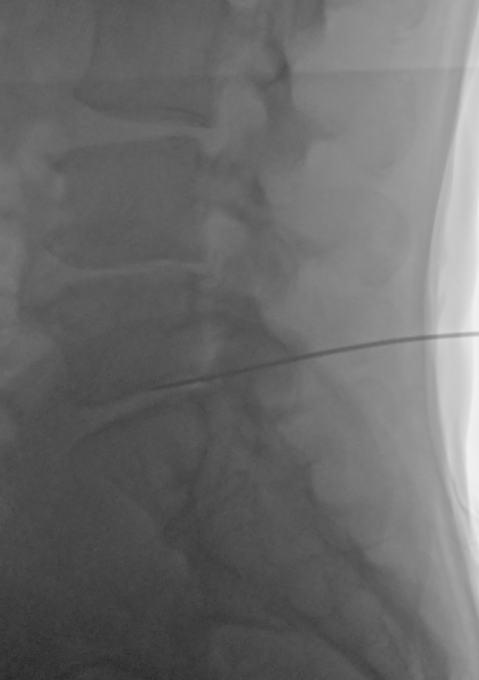

術中画像

PDRは経皮的椎間板再生治療ともいい、患者自身の血液を採取した後、そこから濃縮血小板由来の成長因子を抽出。濃縮血小板由来の成長因子(PRP)と幹細胞上清液を患部の椎間板に注入し、透視装置を使って損傷した椎間板に成長因子と幹細胞上清液を投与します。PLDDと併用することも可能で、日帰りで手術を受けることができます。